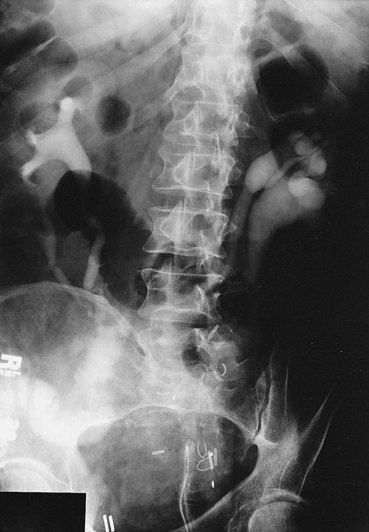

The incidence of intestinal obstruction after abdominal procedures for urinary intestinal diversion differs according to whether the stomach, ileum, or colon is used for the diversion. In patients who have had a segment of stomach or ileum removed for the diversion, there is a 10% incidence of postoperative bowel obstruction requiring treatment. When the colon is used, the incidence of postoperative obstruction requiring an operation is 5% (Table 85–3). Half of the bowel obstructions occur in the early postoperative period. In one series, after radical cystectomy and ileal conduit, 15% of the patients had a mild obstruction in the first 6 months that responded to conservative management, whereas 3% required an operation to relieve the obstruction during this period. The occurrence of obstruction after this 6-month period was much less frequent (Sullivan et al, 1980). More recently, a 10.5% incidence of reoperation for bowel obstruction was noted in a large series of radical cystectomy patients (Varkarakis, 2006). Bowel obstruction can be a morbid event: A significant number of patients who develop obstruction after an ileal conduit and require an operation die. The most common cause of the obstruction is adhesions, followed by recurrent cancer. These two causes account for the great majority of the cases. Volvulus and internal hernia account for far fewer cases (Jaffe et al, 1968). Rarely, severe stenosis or obstruction at the anastomotic suture line occurs. Stenosis is a result of edema, poor technique, or performing the anastomosis on ischemic bowel (Fig. 85–16); obstruction is a result of improper technique.

Intestinal stenosis occurs at two distinct times: in the immediate postoperative period and during the long term. Intestinal stenosis in the immediate postoperative period is due to technical mishaps or edema. Edema resolves by continuing the intestinal decompression, whereas technical mishap requires a reoperation. During the long term, it is likely due to ischemia or perienteric infection. Figure 85–16 shows an upper gastrointestinal tract series of a severe intestinal stenosis caused by ischemia. At the time of the ileoileostomy, the suture line was blue. Chronic symptoms of partial small bowel obstruction occurred in the postoperative period.